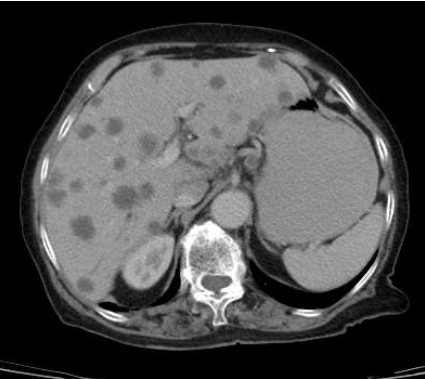

Tomografias de estadiamento evidenciam múltiplos nódulos hipocaptantes bilobares em fígado, sugestivos de

metástases, conforme imagem abaixo: